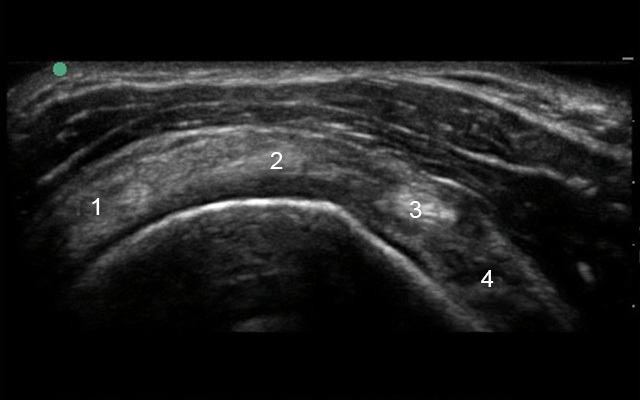

Shoulder Supraspinatus Transverse Image

1. Infraspinatus (IS)

2. Supraspinatus (SS)

3. Biceps Tendon (BT)

4. Subscapularis (SUB)